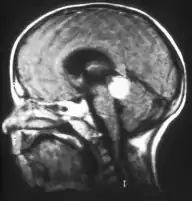

Inherited forms of retinoblastomas are more likely to be bilateral. In addition, inherited uni- or bilateral retinoblastomas may be associated with pineoblastoma and other malignant midline supratentorial primitive neuroectodermal tumors (PNETs) with a dismal outcome; retinoblastoma concurrent with a PNET is known as trilateral retinoblastoma.[13] A 2014 meta-analysis showed that 5-year survival of trilateral retinoblastoma increased from 6% before 1995 to 57% by 2014, attributed to early detection and improved chemotherapy.[14]

In about two-thirds of cases,[23] only one eye is affected (unilateral retinoblastoma); in the other third, tumors develop in both eyes (bilateral retinoblastoma). The number and size of tumors on each eye may vary. In certain cases, the pineal gland or the suprasellar or parasellar region (or in very rare cases other midline intracranial locations) is also affected (trilateral retinoblastoma). The position, size, and quantity of tumors are considered when choosing the type of treatment for the disease.

Traditional ultrasound B scan can detect calcifications in the tumour while high-frequency ultrasound B scan is able to provide higher resolution than the traditional ultrasound and determine the proximity of the tumour with front portion of the eye. MRI scan can detect high-risk features such as optic nerve invasion; choroidal invasion, scleral invasion, and intracranial invasion. CT scan is generally avoided because radiation can stimulate the formation of more eye tumours in those with RB1 genetic mutation.[24]

Aspect of trilateral retinoblastoma on MRI